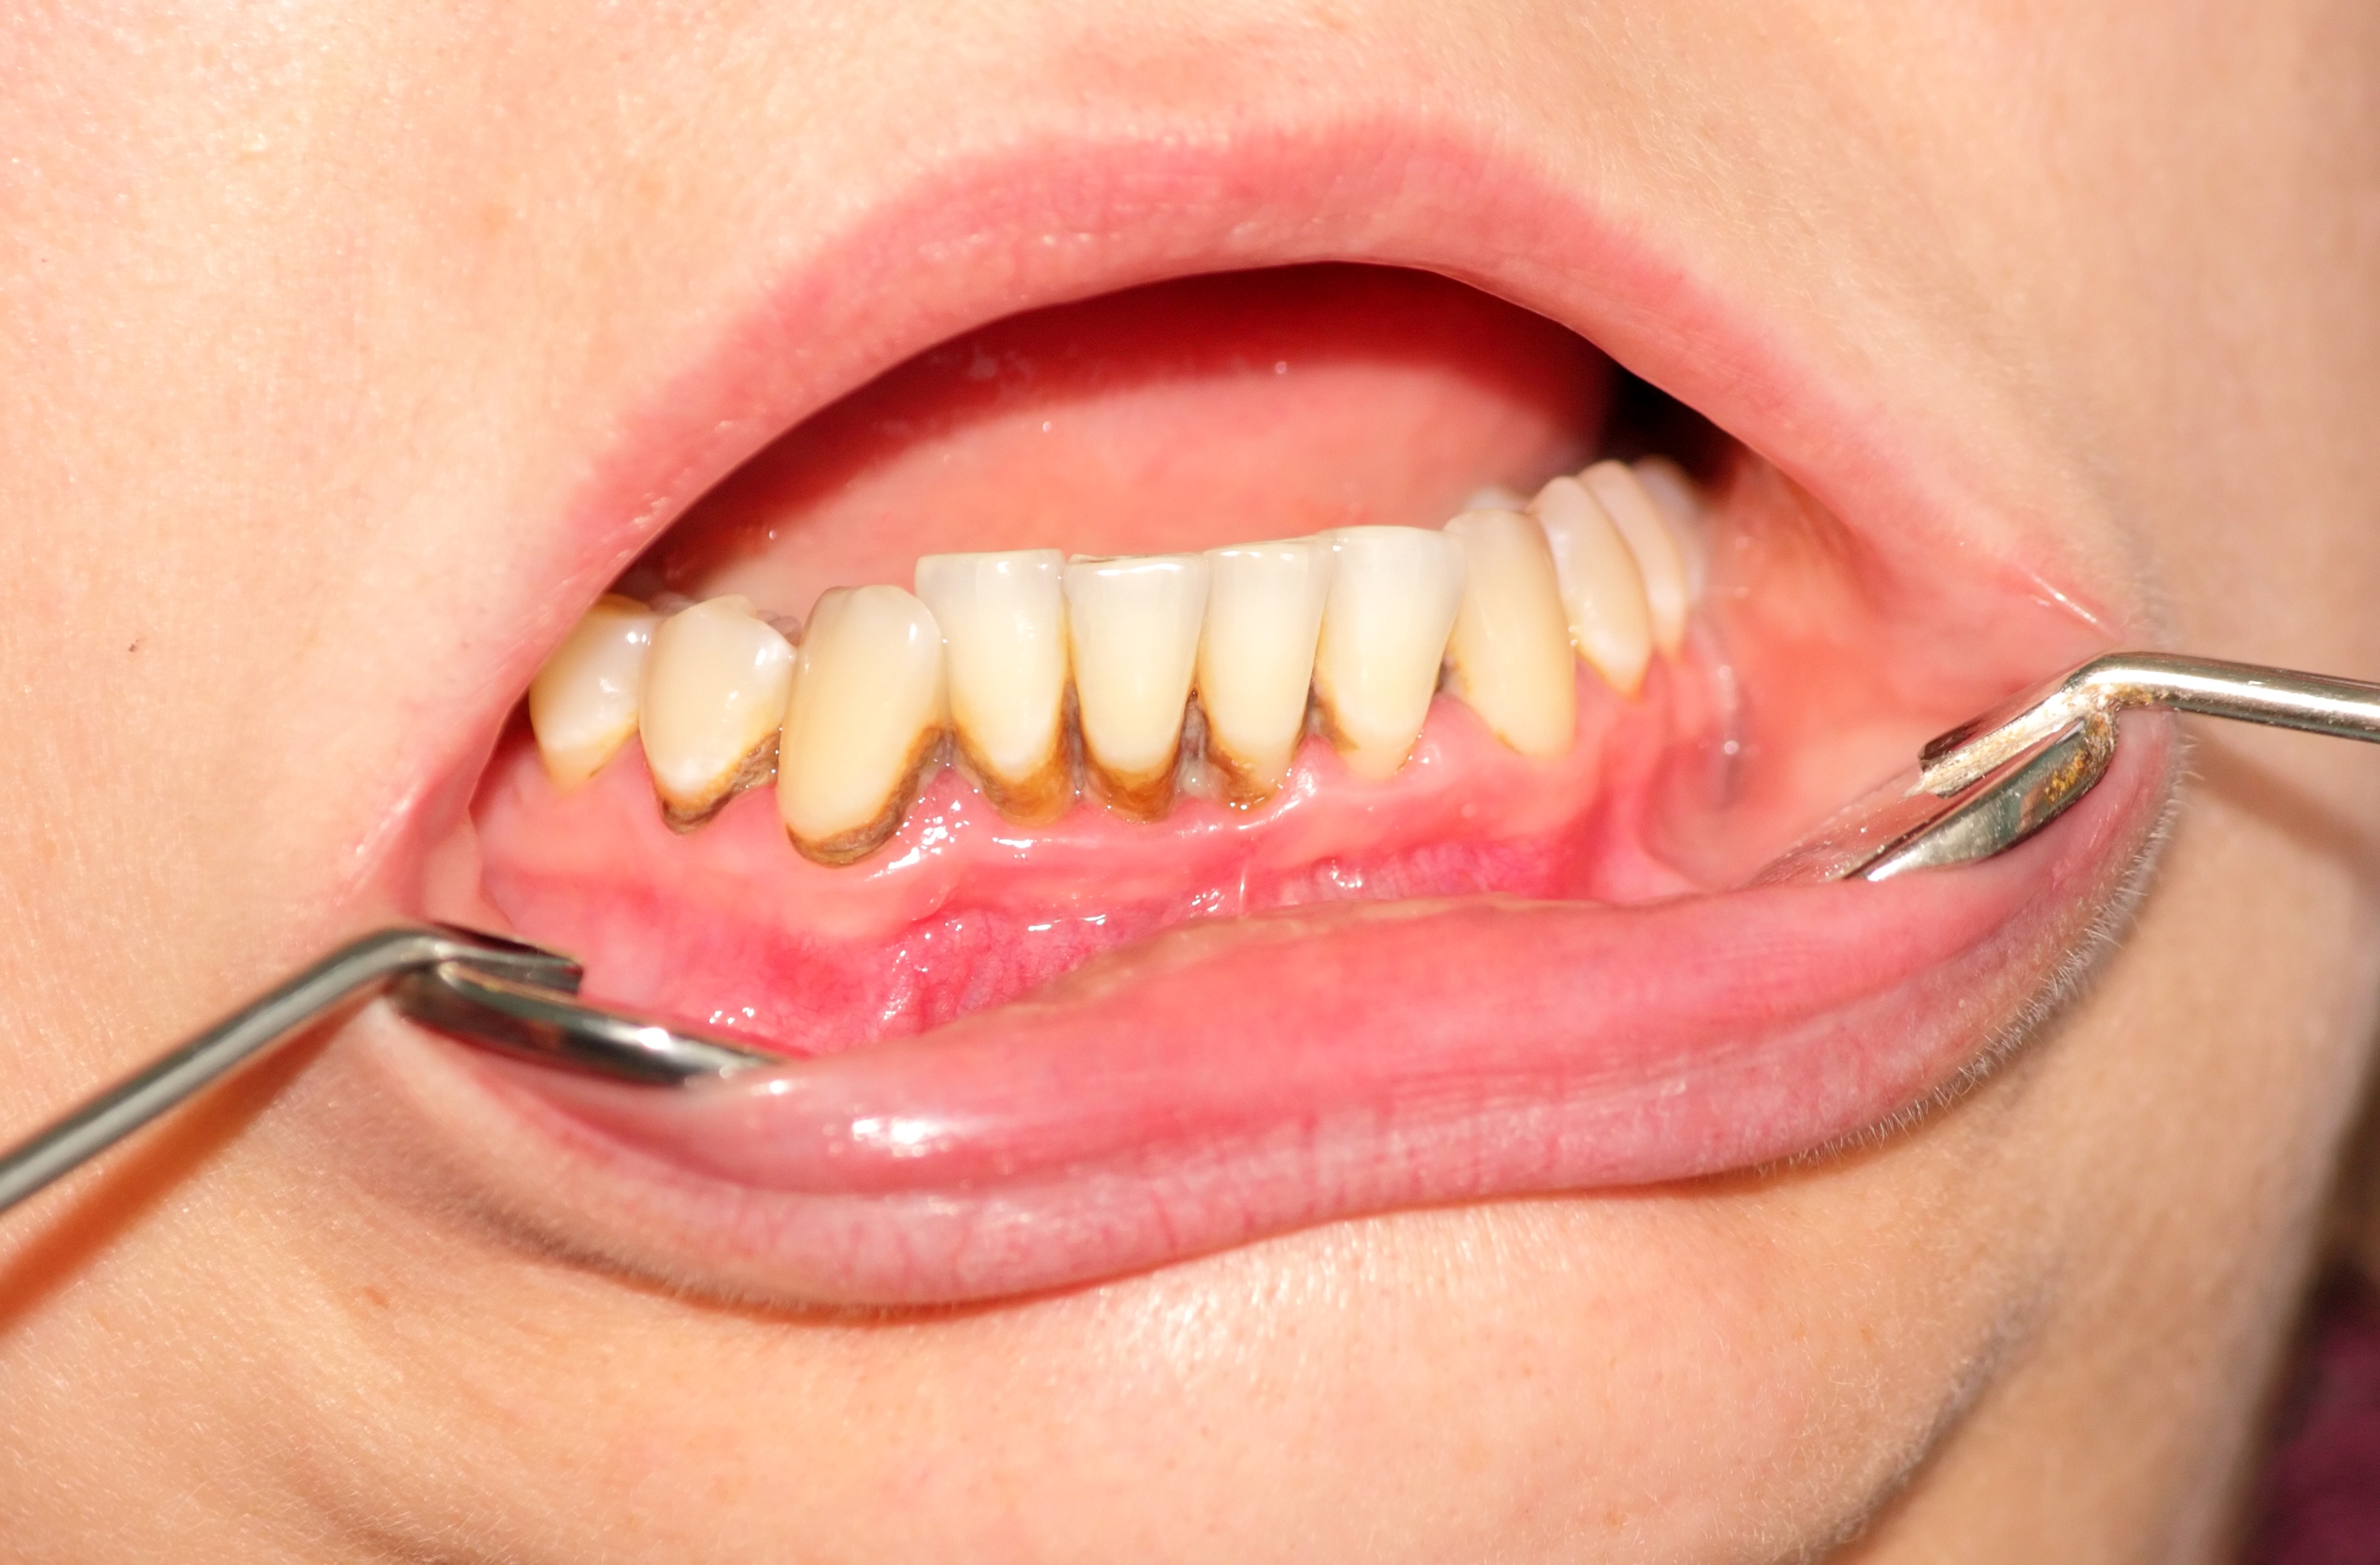

港人常見牙齒問題之一牙周病,成因很簡單,即口腔衞生做得不好,刷牙不徹底導致牙垢積累、細菌繁殖,乃至令牙肉發炎、腫脹,甚至充血。

左偉國介紹,這些致病細菌藏在牙縫裏面及牙肉表面,大約每12小時就會繁殖到一個高峰。因此要早晚刷牙清除牙垢,在繁殖高峰刷走細菌,讓它「由零開始」。而刷牙也並非越用力越好,一些人「刷牙到流牙血才有用」的標準其實並不正確。左偉國「闢謠」,如果牙肉健康、沒有牙周病,以正確手法刷牙並不會造成口腔流血,流血是因為牙齒或牙周已經存在問題。當然,每次刷牙都刷乾淨些,流血的情況就會慢慢緩解。

若已經不幸患有牙周病且病情嚴重,有腫脹、化膿情況,則要先吃消炎藥來救急。但用藥只能先壓下病情,並不治本,需要在用藥後慢慢做口腔清潔直至痊癒。